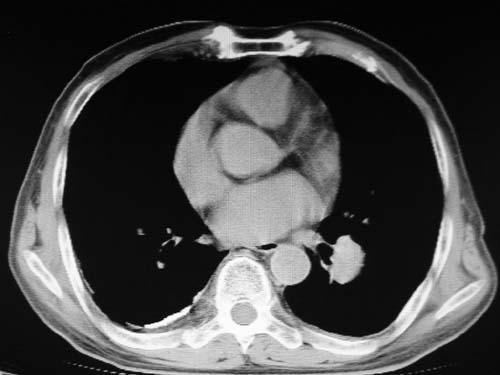

男,80岁

肺动脉瘤。建议先行ct增强扫描

1)考虑左肺动脉瘤可能性大,建议增强。2)右肺上叶继发性肺结核。3)右侧胸膜增厚、钙化,左侧胸膜反应。

肺动脉段突出,左右肺门不等大,左肺门明显增大,肺动脉干及左肺动脉明显增宽,考虑先天性肺动脉狭窄瓣膜狭窄型。

肺动脉高压,左肺动脉瘤样扩张。